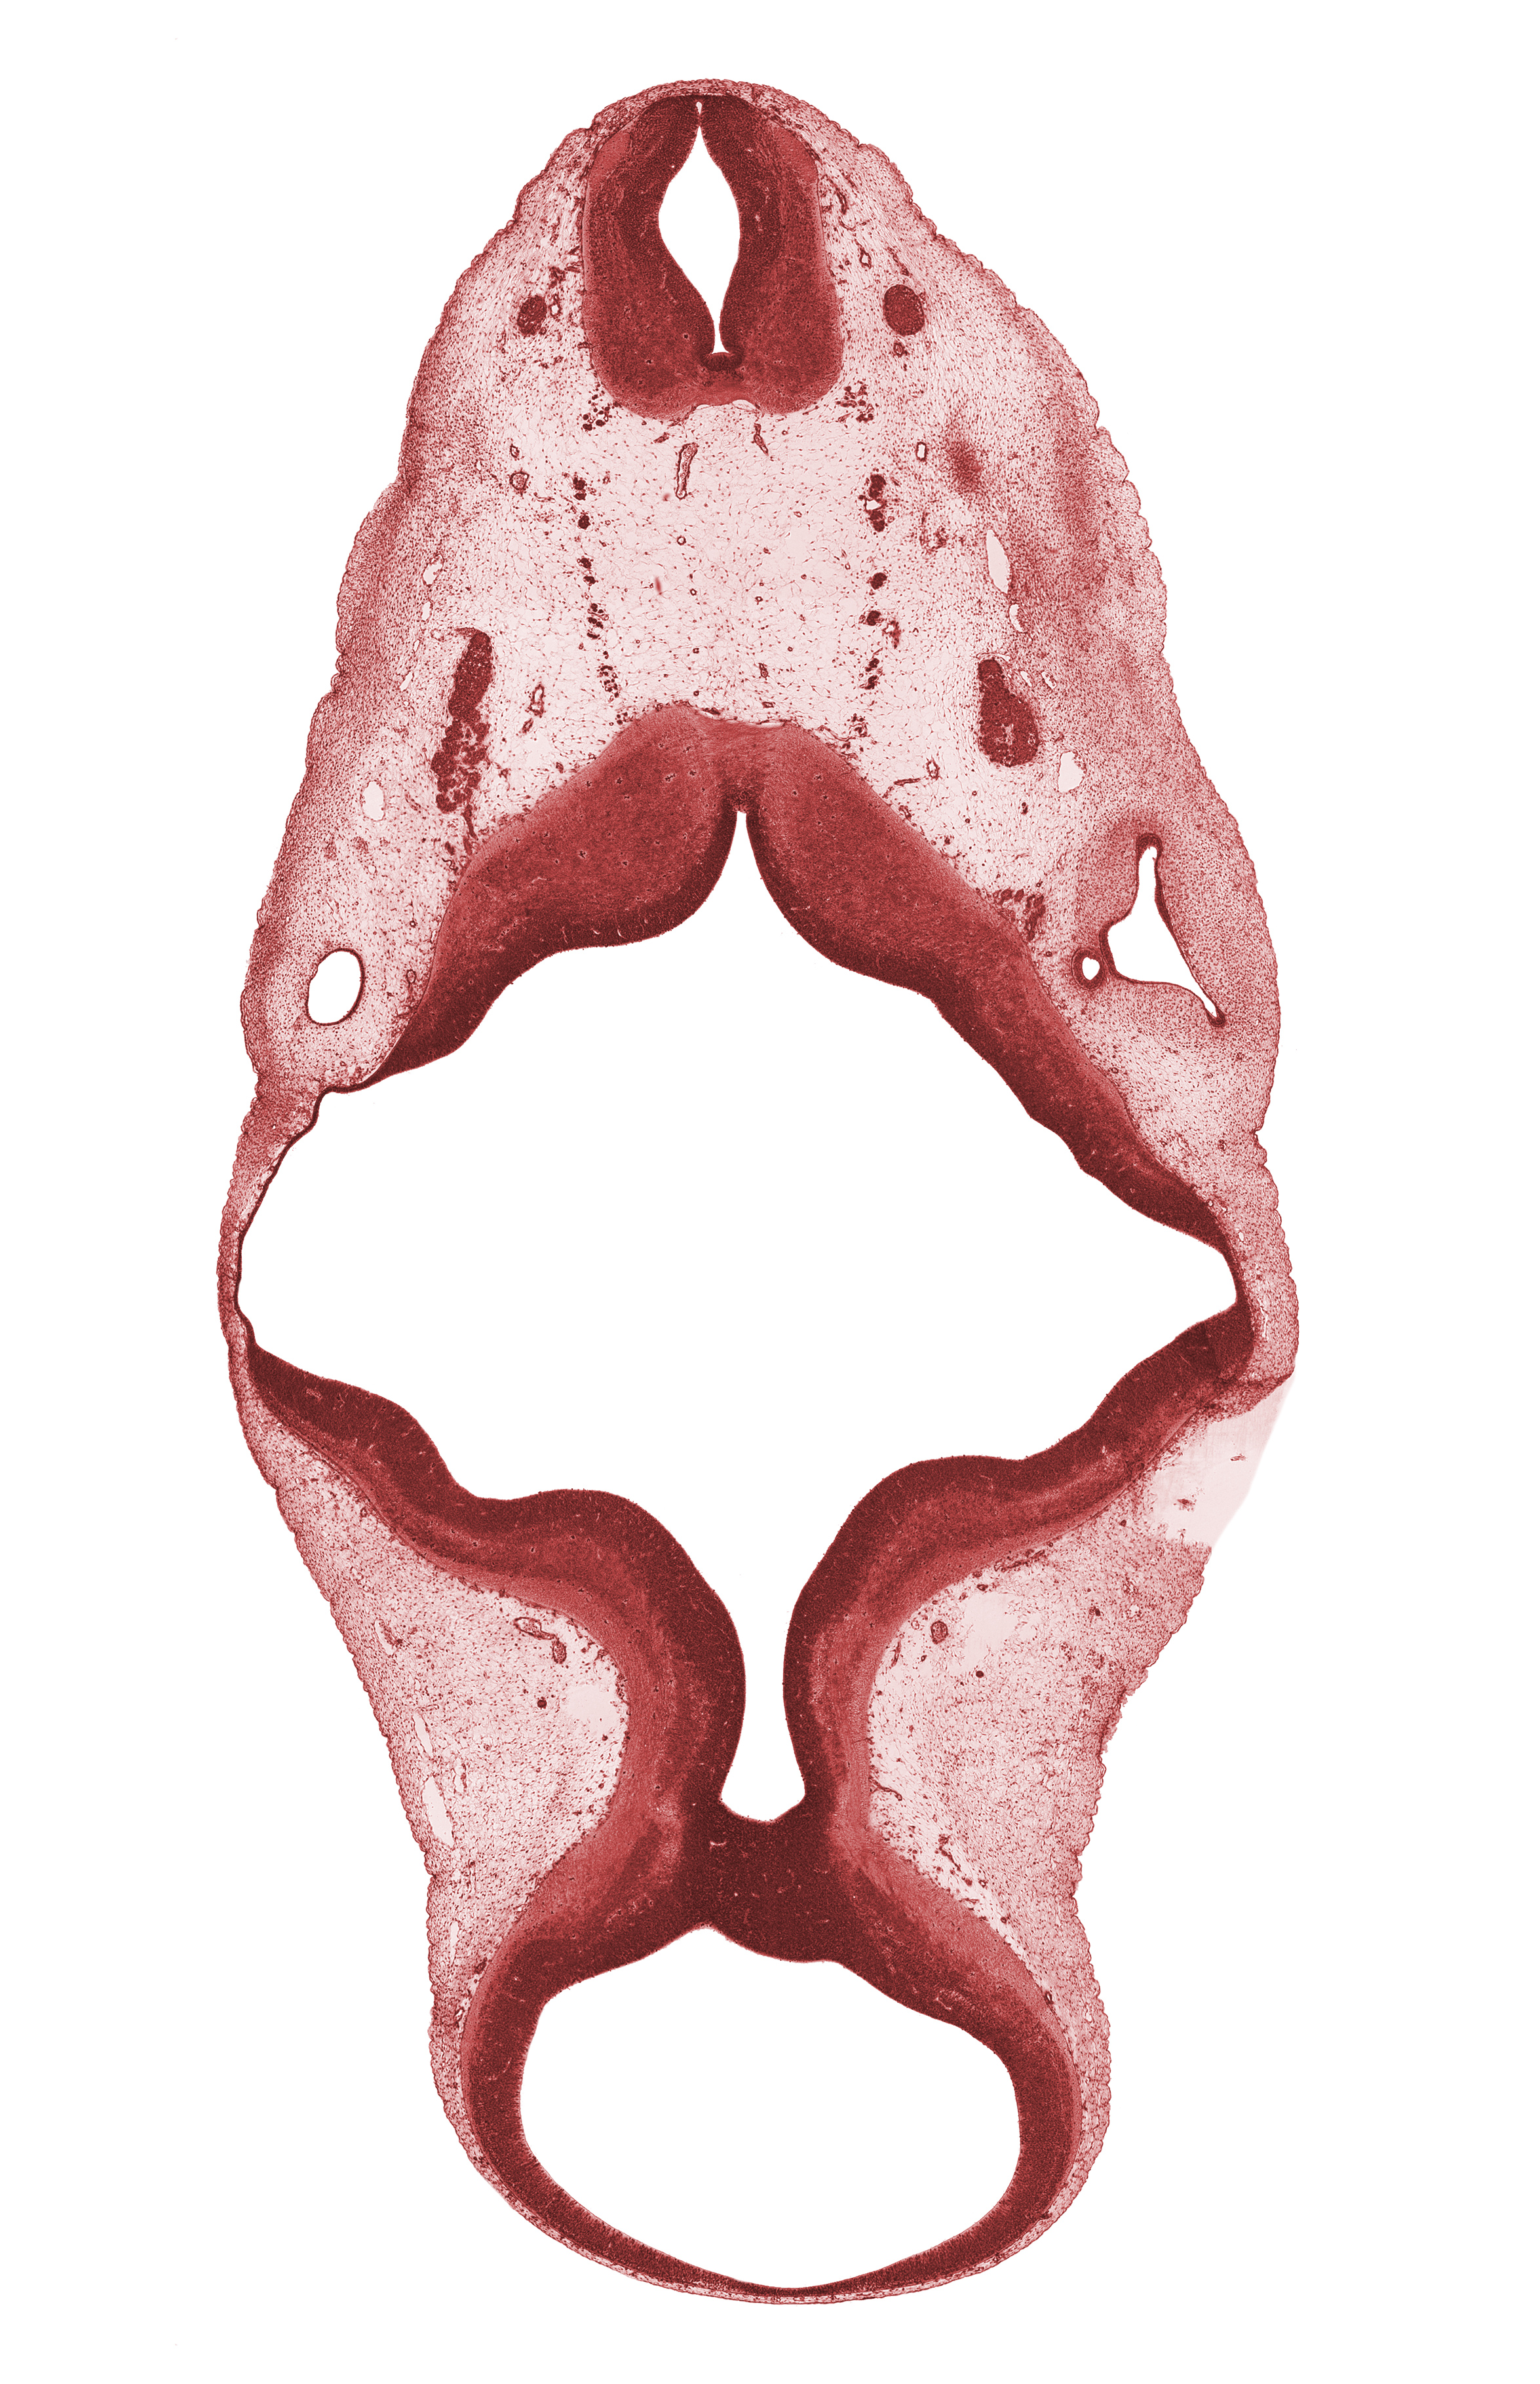

Carnegie Embryo #6520 | Location: 5-03-05

Keywords: C-1 spinal ganglion, C-1 ventral root, accessory nerve (CN XI), alar plate of metencephalon (cerebellum), alar plate(s), basal plate, missing tissue (artifact), oculomotor nerve (CN III), rhombomere 5, roof plate, roof plate of rhombencephalon, root of glossopharyngeal nerve (CN IX), sulcus limitans, superior ganglion of vagus nerve (CN X), trochlear nerve (CN IV), vertebral artery

Source: The Virtual Human Embryo.